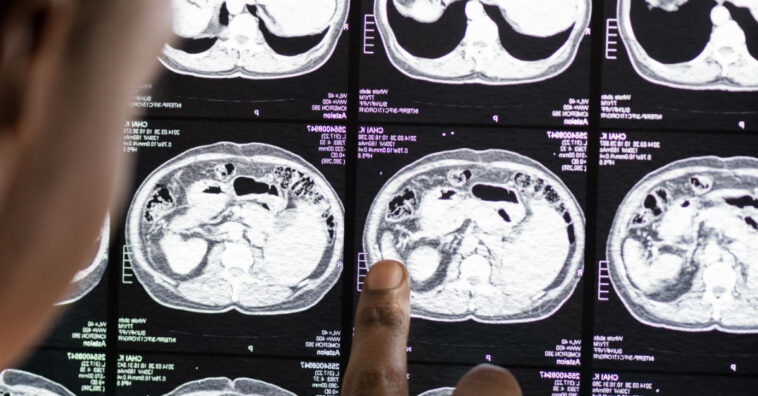

A jovem carregava dentro de si um gêmeo parasita, que inicialmente foi confundido com um tumor comum. Porém, algumas coisas no exame intrigaram os médicos, pois havia estruturas que se assemelhavam a vértebras, costelas e outros ossos. Isso tudo por causa da concentração de cálcio nesses locais, que ficavam mais aparentes no exame de imagem.

O corpo médico decidiu que seria interessante remover o tumor e analisar do que se tratava, já estando desconfiados da rara condição. Assim, ao retirar o caroço de 36 cm de altura, por 16 de largura e 10 de profundidade tiveram uma visão terrível. Era um emaranhado de pelo, osso e pele. Além disso, foi o maior gêmeo parasita encontrado na história.